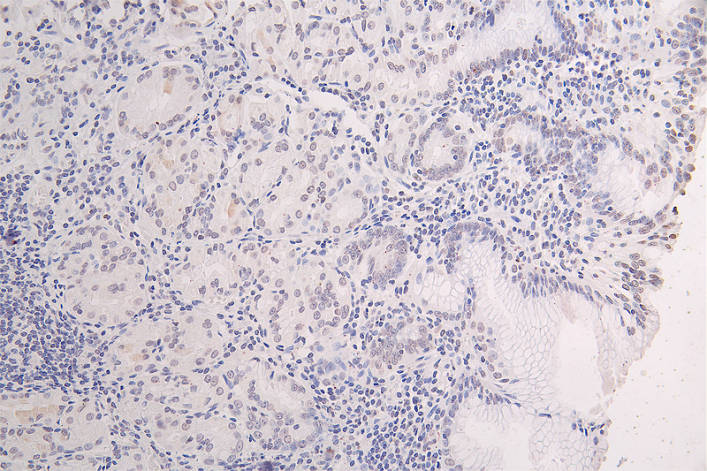

IHC image of CSB-RA943659A0HU diluted at 1:100 and staining in paraffin-embedded human gastric cancer performed on a Leica BondTM system. After dewaxing and hydration, antigen retrieval was mediated by high pressure in a citrate buffer (pH 6.0). Section was blocked with 10% normal goat serum 30min at RT. Then primary antibody (1% BSA) was incubated at 4°C overnight. The primary is detected by a Goat anti-rabbit polymer IgG labeled by HRP and visualized using 0.08% DAB.

產(chǎn)品描述:CSB-RA943659A0HU是針對組蛋白H3變異體Mutated-HIST1H3A(K27位點(diǎn))研發(fā)的重組單克隆抗體,能夠特異性識別該位點(diǎn)突變引起的表觀遺傳學(xué)改變。HIST1H3A是核心組蛋白家族成員,其K27位點(diǎn)的突變與染色質(zhì)重塑異常及基因轉(zhuǎn)錄失調(diào)密切相關(guān),在神經(jīng)系統(tǒng)腫瘤等疾病的分子機(jī)制研究中具有重要價值。本抗體經(jīng)ELISA和免疫組化(IHC)嚴(yán)格驗證,在IHC實驗中推薦使用1:50-1:200的稀釋比例,可清晰檢測石蠟切片或冰凍切片中靶蛋白的特異性表達(dá)定位,且與野生型組蛋白H3無交叉反應(yīng)。適用于探索突變型H3K27在腫瘤發(fā)生發(fā)展中的生物學(xué)功能,支持細(xì)胞模型、動物模型或臨床前樣本的蛋白表達(dá)分析,為表觀遺傳調(diào)控研究、疾病標(biāo)志物篩選及靶向治療機(jī)制探索提供可靠工具。該產(chǎn)品僅限科研用途,不可用于臨床診斷。

Application Recommended Dilution IHC 1:50-1:200 -